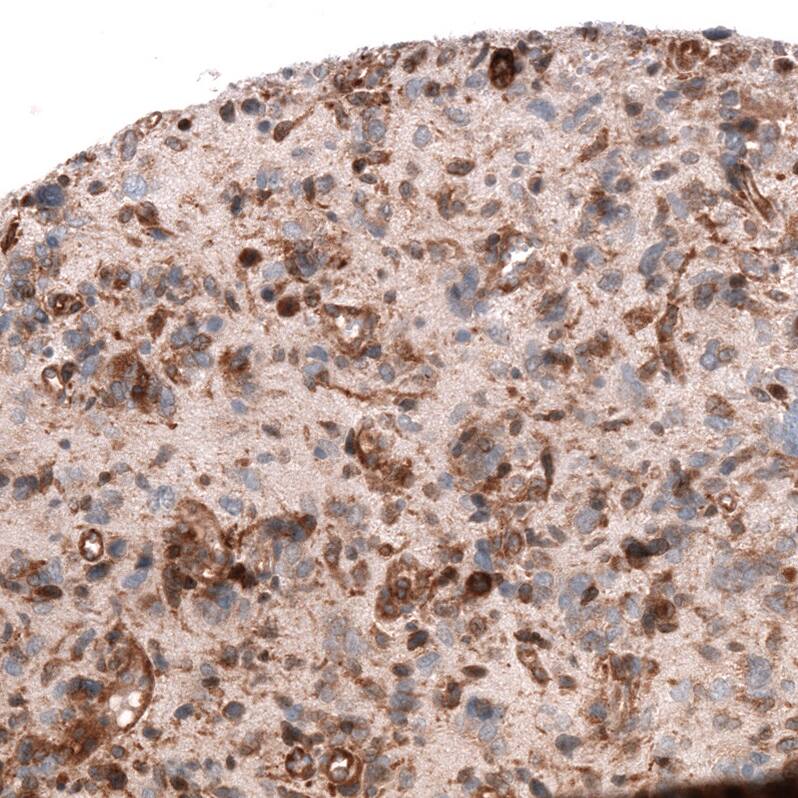

ADAM10 Antibody (CL13808) - Azide and BSA Free Immunohistochemistry-Paraffin: ADAM10 Antibody [NBP3-43825]

Immunohistochemistry-Paraffin: ADAM10 Antibody [NBP3-43825]

Staining of human fallopian tube shows strong membranous positivity in glandular cells.